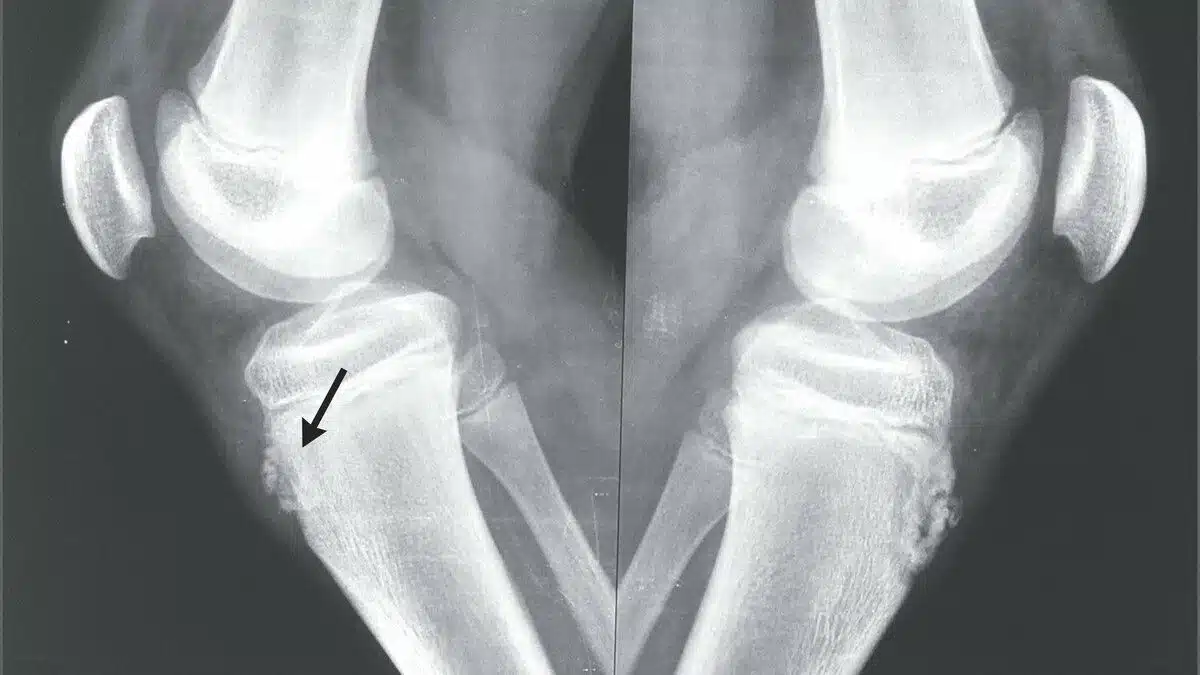

Radiograph of a 12yearold boy with OsgoodSchlatter Disease. Note the Is Osgood Schlatter Bone It is an inflammation of the area just below the knee where the tendon from the kneecap (patellar. Is Osgood Schlatter Bone.